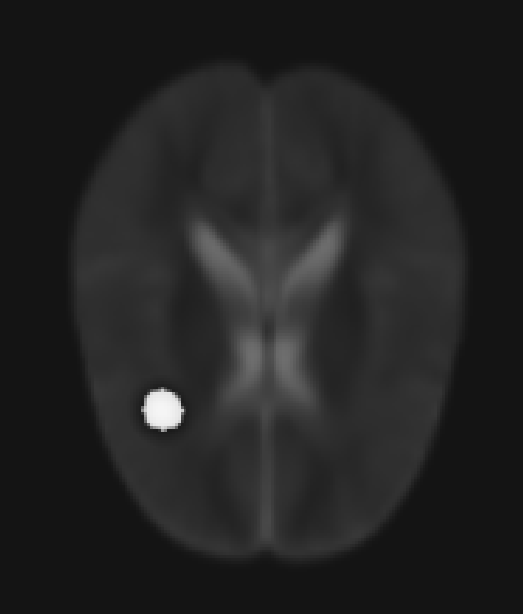

Moreover, the tumor appears abnormally bright or abnormally dark in the DTI output files, depending on the tensor component under consideration. As an example, I included a slice from the Dxx volume of Sim_071_modified_dti.mha.